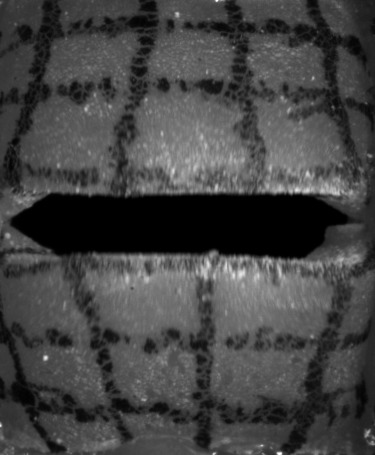

High-speed Camera

The high-speed camera provides a sequence of mono-chromatic images, as shown in Fig. 3. These images can be described as a function of intensities with an image resolution , the screen-space coordinates and with being the currently sampled frame of the video with many frames in total. Then, and denote the estimated motion of the screen-space coordinate at time along the longitudinal and lateral axis, respectively, resulting in the motion vector field:

We applied the sparse to dense optical flow algorithm based on the Lucas-Kanade feature tracker with pyramids by [25], which is available in OpenCV [26]. Such dense optical flow algorithm estimates a motion for every pixel of the input image, but tends to oversmooth flows (see Fig. 4(a)), which produces artifacts at edges. To mitigate this problem, we apply a mask (see Fig. 4(b)), which helps to distinguish the vocal folds from the gap between them. We use the intensity values for the mask segmentation with a subsequent median filter for more robustness to noise. Using the mask (see Fig. 4(c)), we set the motion vectors inside the gap explicitly to zero vectors, since there is no vocal fold movement. For consistency with the remaining data, the motion in the image plane is converted to physical domain units. The high-speed images and the resulting optical flows are discrete in space (individual pixels) and in time (individual frames). We interpolate the resulting discrete vector piecewise bilinearly in space with continuity and we interpolate quadratically with continuity in time to extract a continuous time-dependent two-dimensional vector field.